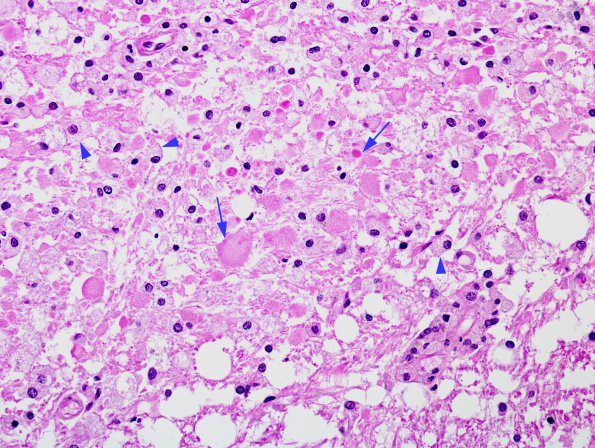

5B2,3 Higher magnification of the histologic appearance of the lesion is represented by a confluent collection of macrophages, reactive astrocytes and axonal spheroids. Spheroids are labeled with arrows and macrophages with arrowheads (H&E)